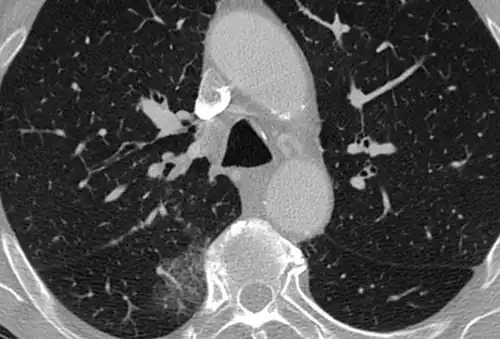

High-resolution CT image showing ground-glass opacities in the periphery of both lungs in a patient with COVID-19 (red arrows). The adjacent normal lung tissue with lower attenuation appears as darker areas.

CT image in patient with COVID-19 showing bilateral ground-glass opacities at the periphery of both lungs.

Ground-glass opacity is among the most common imaging findings in patients with confirmed COVID-19.[16][17] One systematic review found that among patients with COVID-19 and abnormal lung findings on CT, greater than 80% had GGOs, with greater than 50% having mixed GGOs and consolidation.[16] GGOs with mixed consolidation has most often been found in elderly populations.[18] Several studies have described a pattern among initial, intermediate, and hospital discharge imaging findings in the disease course of COVID-19. Most commonly, initial CT imaging reveals bilateral GGOs at the periphery of the lungs. During initial stages, this is most often found in the lower lobes, although involvement of the upper lobes and right middle lobe has also been reported early in the disease course.[16][18] This is in contrast to the two similar coronaviruses, SARS and MERS, which more commonly involve only one lung on initial imaging.[19][20] As the COVID-19 infection progresses, GGOs typically become more diffuse and often progress to consolidation.[11][18] This is sometimes accompanied by the development of a crazy paving pattern and interlobular septal thickening.[18] In many cases the most severe pulmonary CT abnormalities occurred within 2 weeks after symptoms began.[17] At this point, many individuals begin showing resolution of consolidation and GGOs as symptoms improve. However, some patients have worsening symptoms and imaging findings, with further increase in septal thickening, GGOs, and consolidation. These patients may develop lung "white-out" with progression to acute respiratory distress syndrome (ARDS) requiring treatment escalation.[17][21]